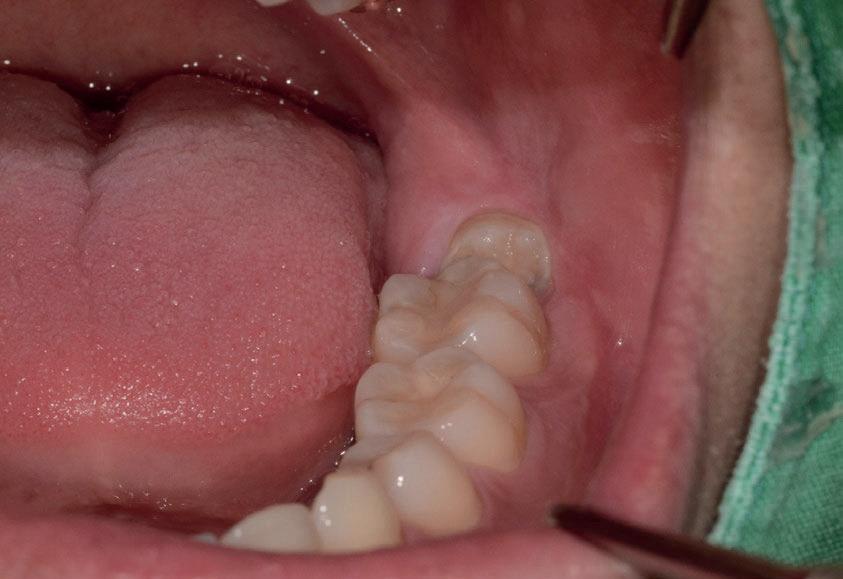

Questo è un paziente di 22 anni ed essendo un amico, ho potuto ben documentare il caso con il suo consenso: il suo dente del giudizio inferiore sinistro è stato estratto utilizzando il manipolo dritto. Figg. 143-149

Figg. 143-149 - Caso 1, paziente di 22 anni: tecnica di estrazione con divisione orizzontale utilizzando il manipolo dritto. Fig. 143 Fig. 144 Fig. 145 Fig. 146 Fig. 147 Fig. 148 Fig. 149

In generale l’estrazione di un dente del giudizio inferiore, utilizzando il manipolo dritto, richiede un’incisione posteriormente alla superficie mesiale del secondo molare. Se il dente non è incluso, la rimozione di osso vestibolare non è necessaria, ma al contrario, più il dente è in profondità e più osso vestibolare dovrà essere rimosso. Una volta che l’osso vestibolare è stato rimosso, il dente viene sezionato vestibolo-lingualmente e separato in una metà mesiale e una distale, utilizzando una leva. Il segmento distale del dente che non giace nel sottosquadro della regione distale del secondo molare viene rimosso per primo e poi viene rimosso quello mesiale. Figg. 150-156

Il seguente caso chirurgico è di un 4.8 mesio-inclinato e parzialmente incluso. Dopo un’incisione a busta, il

dente è stato separato al centro per fare una coronectomia, prima della porzione distale e successivamente della porzione mesiale. Facendo leva quindi è stato possibile rimuovere le radici unite. Figg. 165-172

Abbiamo estratto il dente del giudizio inferiore di destra in una paziente di 22 anni, un’amica, utilizzando il manipolo dritto, con il proposito di fare delle foto dell’intervento. Figg. 173-179